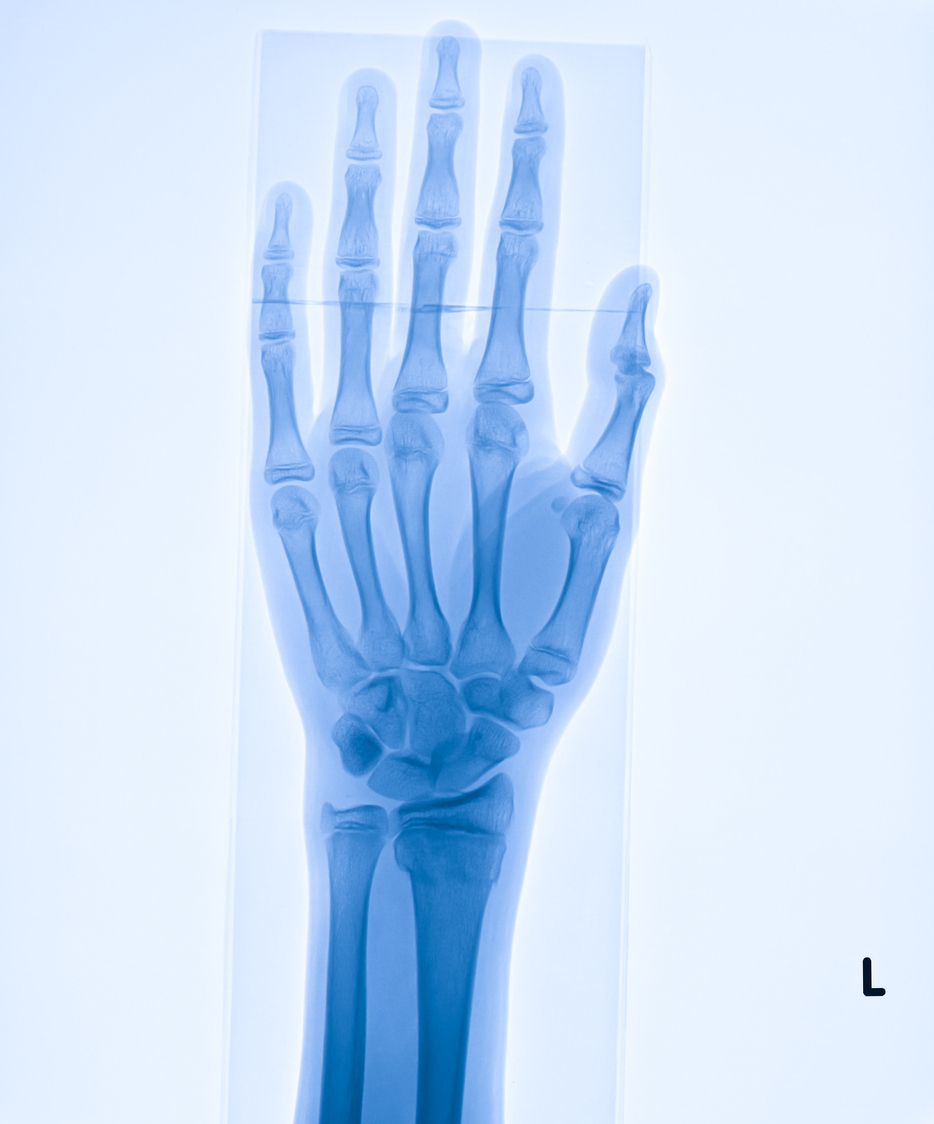

Common Types of Wrist Surgery

Pain in the hand and wrist may have many causes, including injuries and health conditions. Some of these injuries and conditions, when diagnosed early, may not need invasive surgery. However, this isn’t always possible. There are circumstances when wrist surgery is necessary to help bring you relief and restore your mobility. Here are some common…